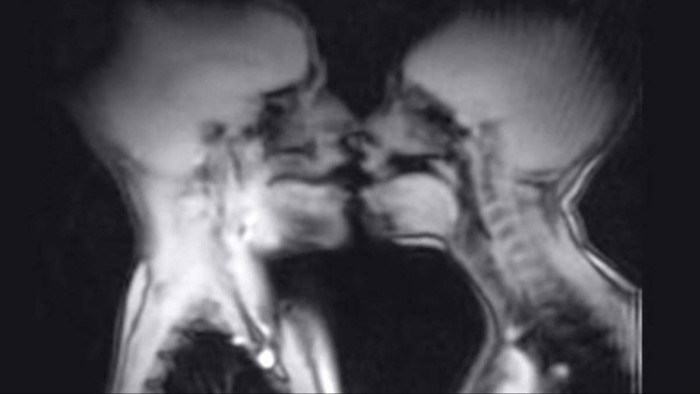

A 28-year-old woman refused to be the punchline, so researchers did something way weirder than a “fun date night” experiment, they put a couple into an MRI scanner to watch what intimacy does to human anatomy. The whole premise sounds like a sci-fi dare, but the goal was brutally specific: capture magnetic resonance images during coitus and see what changes inside.

It gets complicated fast, because this was not just about one body part doing one job. The scans were meant to track male anatomy during intercourse, including that missionary-position detail where the penis reportedly shifts into a boomerang-like shape, and also female arousal changes, like the uterus lifting and the anterior vaginal wall lengthening, even without intercourse.

Their aim was to contribute to the understanding of human anatomy, specifically how the body responds during sexual activity. The results of their experiment were published in a 1999 entry of the British Medical Journal, where they concluded that capturing magnetic resonance images of male and female genitalia during coitus is not only feasible but also provides valuable insights into anatomical changes that occur during sexual intercourse.

This groundbreaking study has opened doors to further research and understanding of human sexual physiology. One of the key findings from the MRI scans was the observation of the penis's shape during intercourse, particularly in the missionary position.

The images revealed that the penis takes on a boomerang-like shape, with approximately one-third of its length consisting of the root of the penis. This anatomical detail adds to the understanding of how the male body functions during sexual activity, providing a visual representation of what occurs internally.

Additionally, the study examined female sexual arousal and its effects on the anatomy of the uterus and vaginal walls. The researchers noted that during female sexual arousal, even without intercourse, the uterus is elevated, and the anterior vaginal wall lengthens.

Interestingly, the size of the uterus itself does not increase during arousal, which raises questions about the physiological mechanisms at play during sexual excitement. While these findings were certainly valuable, the research also uncovered a puzzling phenomenon that has left scientists scratching their heads.